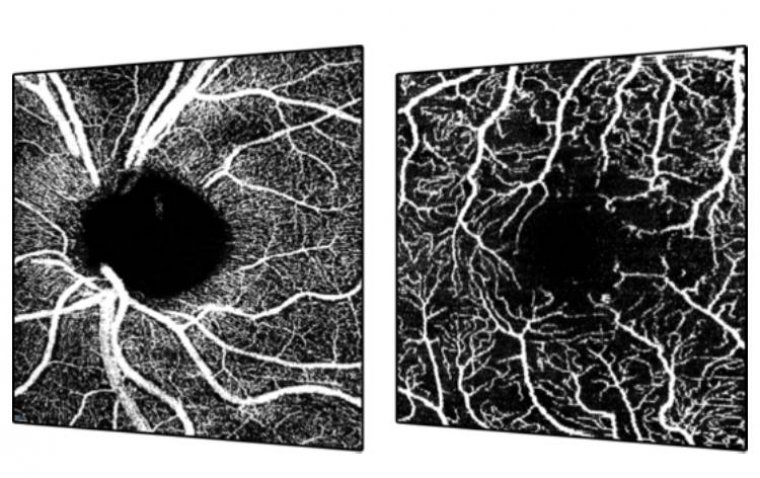

Особенно важно, что пресет OCTA 125 кГц позволяет визуализировать кровоток даже в мельчайших сосудах при минимизации артефактов, создавая четкие и детализированные изображения капиллярной сети. Деннис М. Маркус (Dennis M. Marcus), доктор медицины, главный исследователь клинического испытания, отметил значение сокращения времени сканирования: «Уменьшение времени сканирования при OCTA без снижения разрешения — огромный шаг вперед не только для SPECTRALIS, но и для всей индустрии. Сочетание скорости и качества изображения устраняет барьеры и открывает путь для широкого внедрения. Я полагаю, что все больше врачей начнут положительно относиться к идее использования OCTA в рамках стандартного клинического обследования пациентов из группы риска».